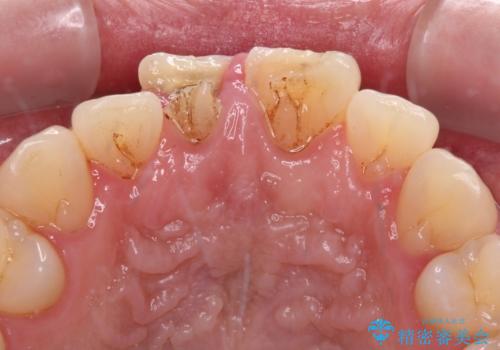

- 転倒により前歯を折ってしまったとのことで来院された患者様です。

右側の前歯は歯茎の中にまで及ぶ深い破折線があり、神経組織は既に失活していました。

左側の前歯は大きく歯冠が欠けてはいましたが、神経の生活反応が認められました。

失活した歯は、根管治療を行った後に部分矯正により歯根を引っ張り出し、歯周外科処置により左右の歯肉の位置が揃えることとしました。